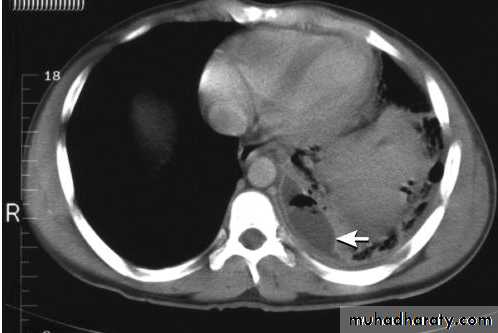

Empyema.

A computed tomography scan shows a posterior left pleural fluid collection (arrow) containing air (dark) and surrounded by thickened pleura.

The thickened pleura appears to be split by the lenticular fluid collection.